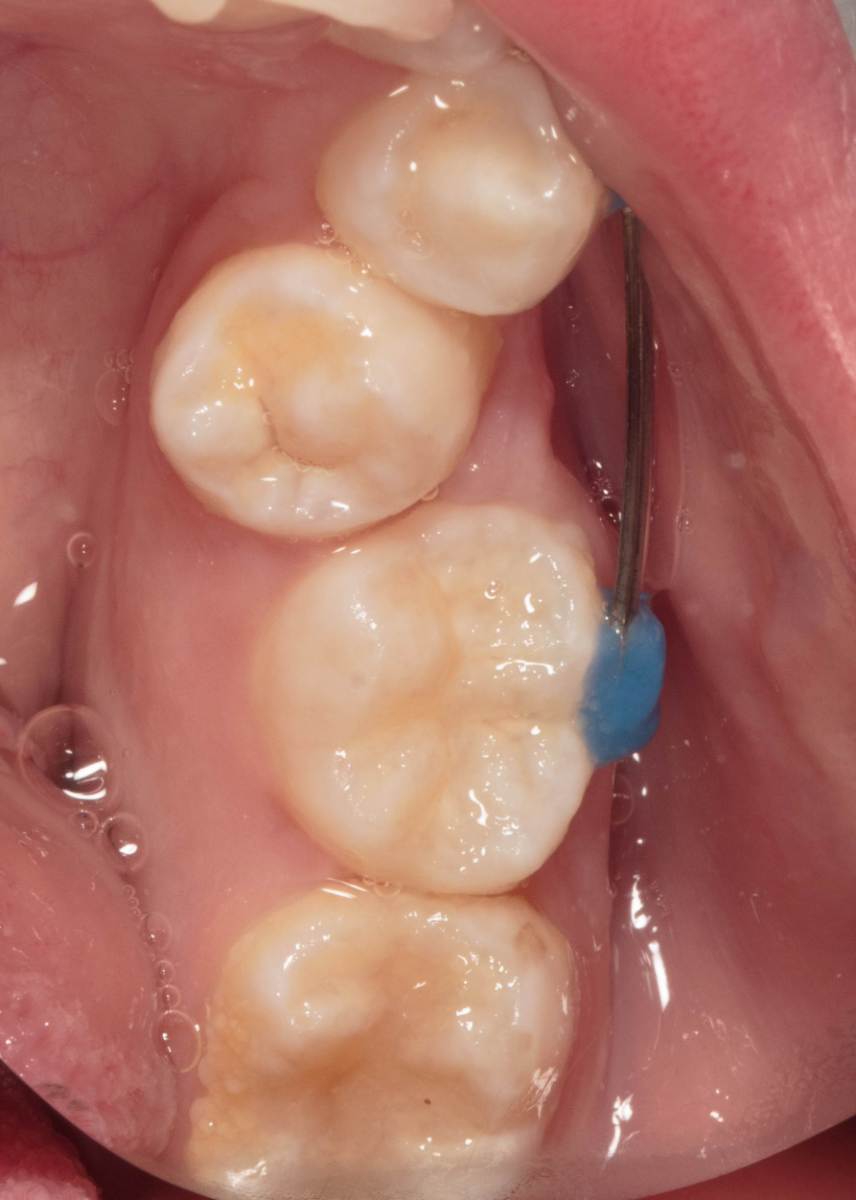

Женька Опубликовано 28 ноября, 2025 Поделиться Опубликовано 28 ноября, 2025 Всем привет, коллеги! 14 лет, терапевты ставят трещину по КТ (снимков до, к сожалению нет, косяк, каюсь). чуть сепарировав зуб и глянув на зуб под отлетевшим куском пломбы трещина "подтвердилась". Кейс на фото. Из интересного - маленький реколл в 1.5 года и спокойное перемещение зуба брекетами! 4 1 2 Ссылка на комментарий